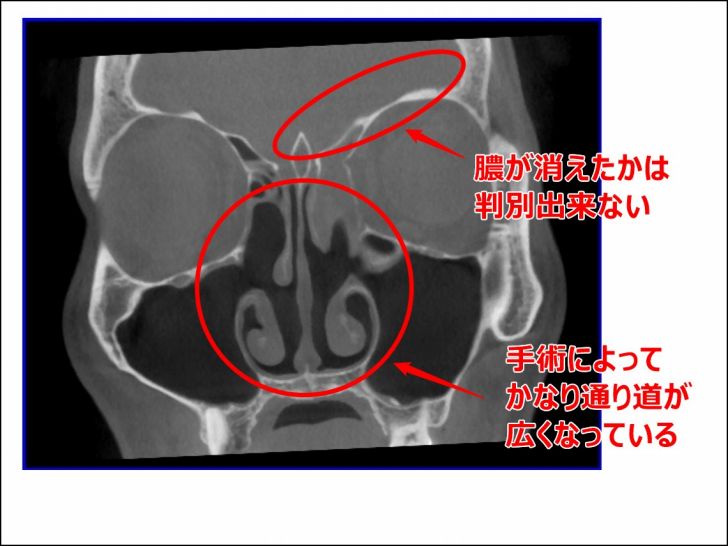

2015年8月の副鼻腔

5月に手術をした方が良いと診断され、6月に手術を実施。

その後8月頃に一度頭痛が悪化したことがあったため、その時にもCTを撮影しました。

その時の画像です。

▼2015年8月のCT画像

1度目の手術で鼻の中央辺りがかなり変わったことが分かります。

[su_note note_color=”#ffffcc” radius=”0″]

【画像解説】

手術前の画像と比べてもらえれば分かりますが、複雑に迷路のようになっていた鼻の中央がごっそり削られてなくなっています。

こうやって鼻の通り道をよくして、膿が排出されやすくするための手術だったわけですね。

ただ、前頭洞周辺にある膿が排出されているのかはこの画像では判別しにくかったです。

[/su_note]